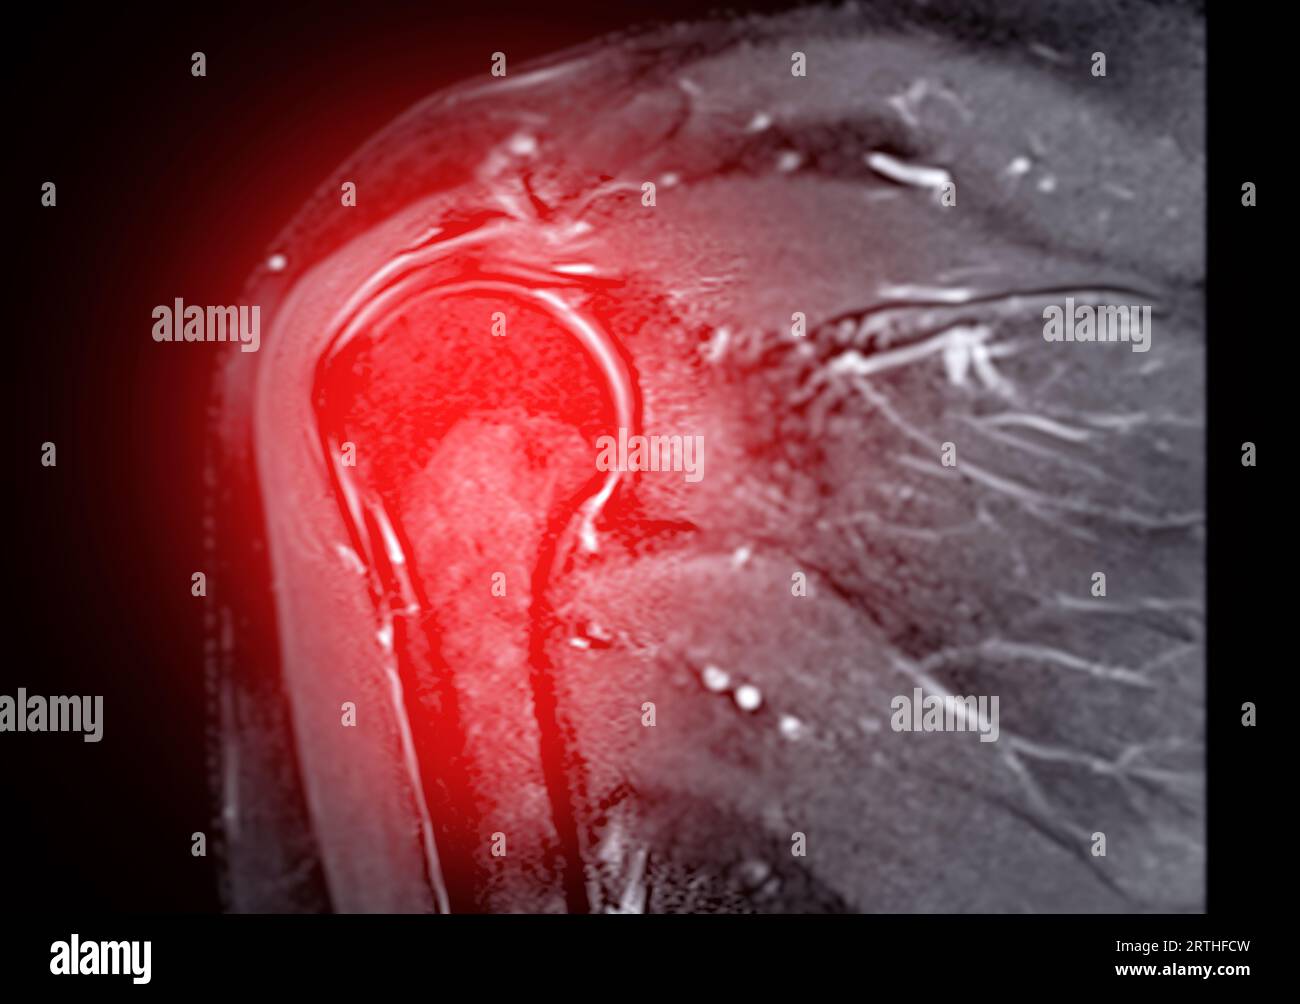

Resonance Imaging or MRI of Shoulder Joint for diagnostic shoulder pain Stock Photo Alamy What Can Mri Of Shoulder Detect A shoulder mri can diagnose tears of the rotator cuff, labrum, and tendons. a shoulder mri is a test that uses a magnetic field to take pictures of your shoulder. magnetic resonance imaging, or mri, uses a magnet to examine the inside of your body, useful for diagnosing shoulder pain and. the evaluation of the shoulder, and. What Can Mri Of Shoulder Detect.

What Can Mri Of Shoulder Detect . magnetic resonance imaging (mri) of the shoulder uses a powerful magnetic field, radio waves and a computer to produce. a shoulder mri is a test that uses a magnetic field to take pictures of your shoulder. The mri allows accurate assessment of. in particular, the images include your muscles, ligaments, and cartilage as well as any other components. magnetic resonance imaging, or mri, uses a magnet to examine the inside of your body, useful for diagnosing shoulder pain and. magnetic resonance imaging (mri) of the shoulder is done to: what can a shoulder mri diagnose? the evaluation of the shoulder, and especially its soft tissue structures, is best done with an mri. Learn more about what it’s for,. A shoulder mri can diagnose tears of the rotator cuff, labrum, and tendons.